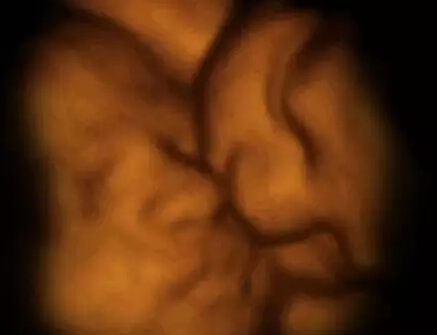

4-D扫描图显示了双胞胎在子宫中活动的情况。胎儿为了争夺生存空间和养料而彼此推挤。

在这里你甚至可以清晰辨认出画面前方这个双胞胎胎儿手上的根血管。